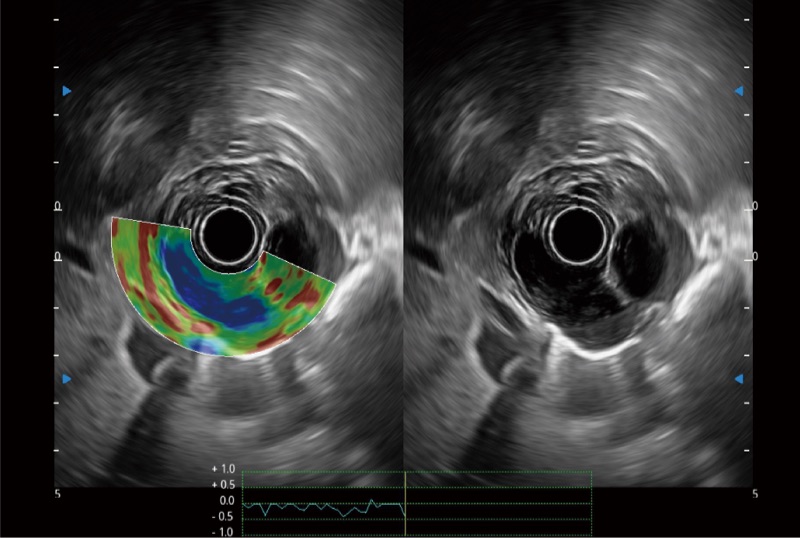

• 弹性成像

位移矫正技术

不可靠区域自动剔除

弹性定量分析软件